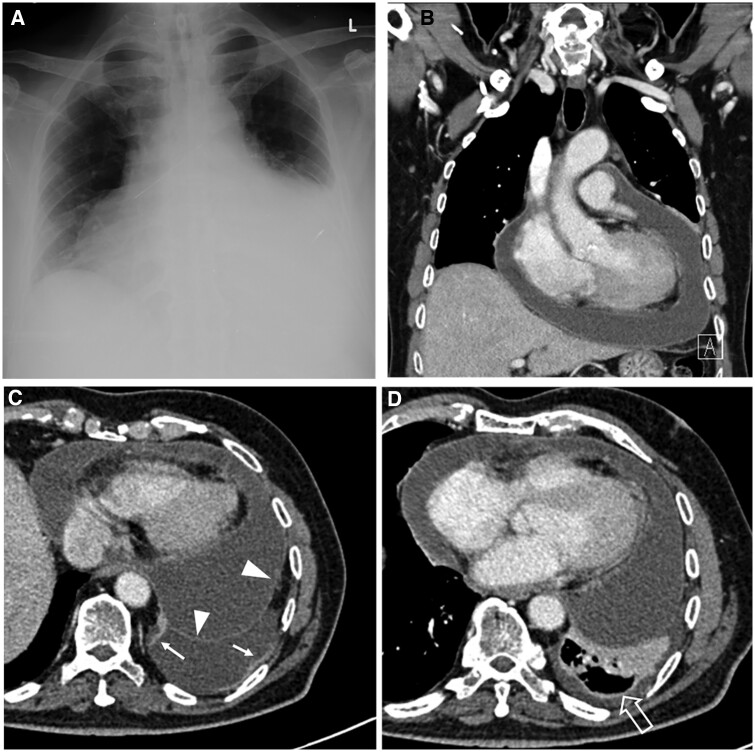

Tuberculosis (TB) remains the leading cause of death from a single infectious agent globally, despite being a potentially curable disease. This disease typically affects the lungs but may involve many extrapulmonary sites, especially in patients with risk factors such as HIV infection. The clinical features of extrapulmonary TB may mimic many different disease entities, particularly at less common thoracic sites such as the heart, chest wall, and breast. Imaging has an important role in the early diagnosis of TB, helping to detect disease, guide appropriate laboratory investigation, demonstrate complications, and monitor disease progress and response to treatment. Imaging supports the clinical objective of achieving effective treatment outcome and complication prevention. This review aims to highlight the imaging spectrum of TB affecting both pulmonary and extrapulmonary sites in the thorax. We also briefly provide key background information about TB, such as epidemiology, pathogenesis, and diagnosis.